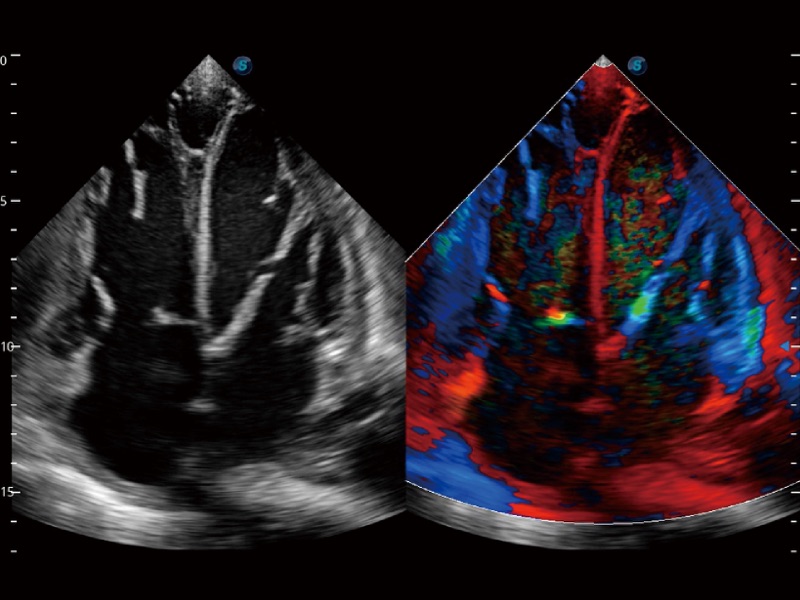

• 心血管应用